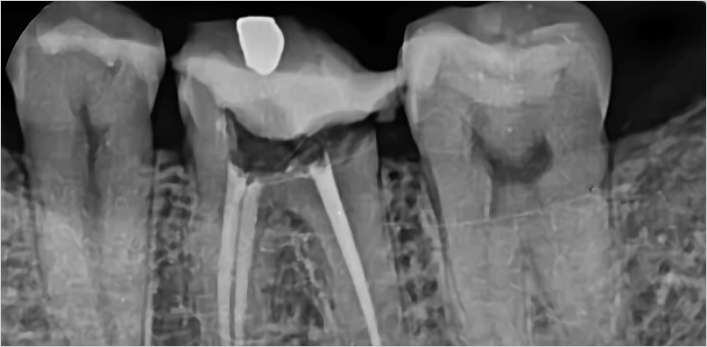

미세현미경 신경치료 치료사례

서울스마트치과는 결과로 증명합니다.

치료 전

치료 후

김** 환자분 (신경치료 진행 후 지르크라운으로 치료)

왼쪽아래 어금니 통증으로 방문,

보철물 제거 후 확인해보니 남은 치질이 별로 없어 post 추가 및 신경치료 진행 후 지르크라운으로 치료

위 치료 사례는 서울스마트치과에서 직접 치료를 받고, 환자 본인의 동의를 얻어 게재된 사진으로 무단 인용, 도용, 재배포 시 민/형사상 책임을 질 수 있습니다.